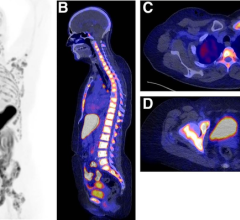

April 5, 2023 — According to an accepted manuscript published in ARRS’ own American Journal of Roentgenology (AJR), a ...